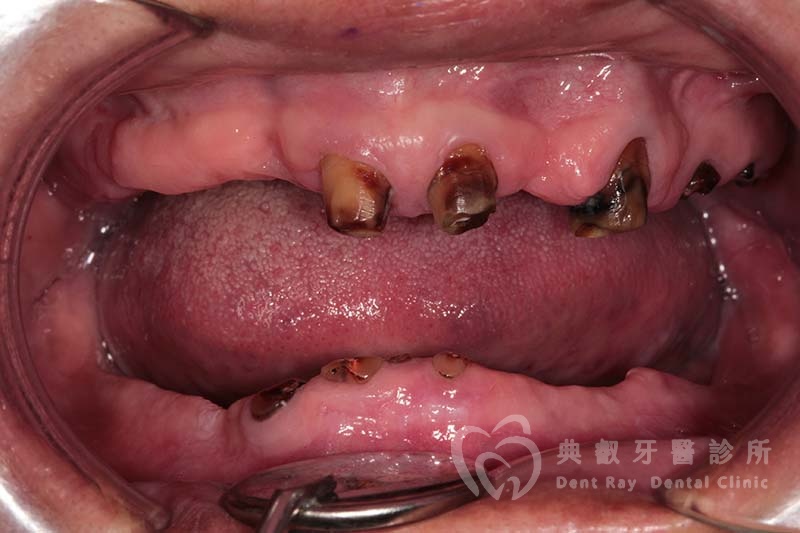

假牙案例十一

術前

術後